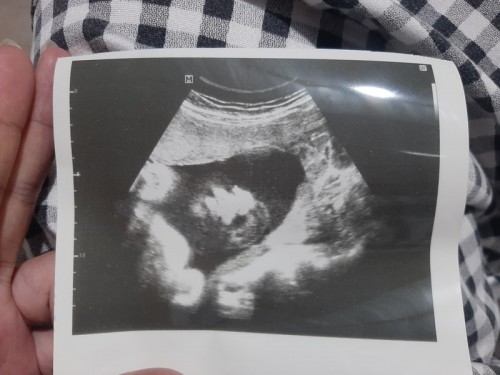

น้ำหนักของเบบี๋

ผม 28w4d นน.1470กรัมแล้ว ครับ แม่ๆบ้านอื่น น้อง นน.เท่าไหร่ กันบ้างแล้วครับ😊